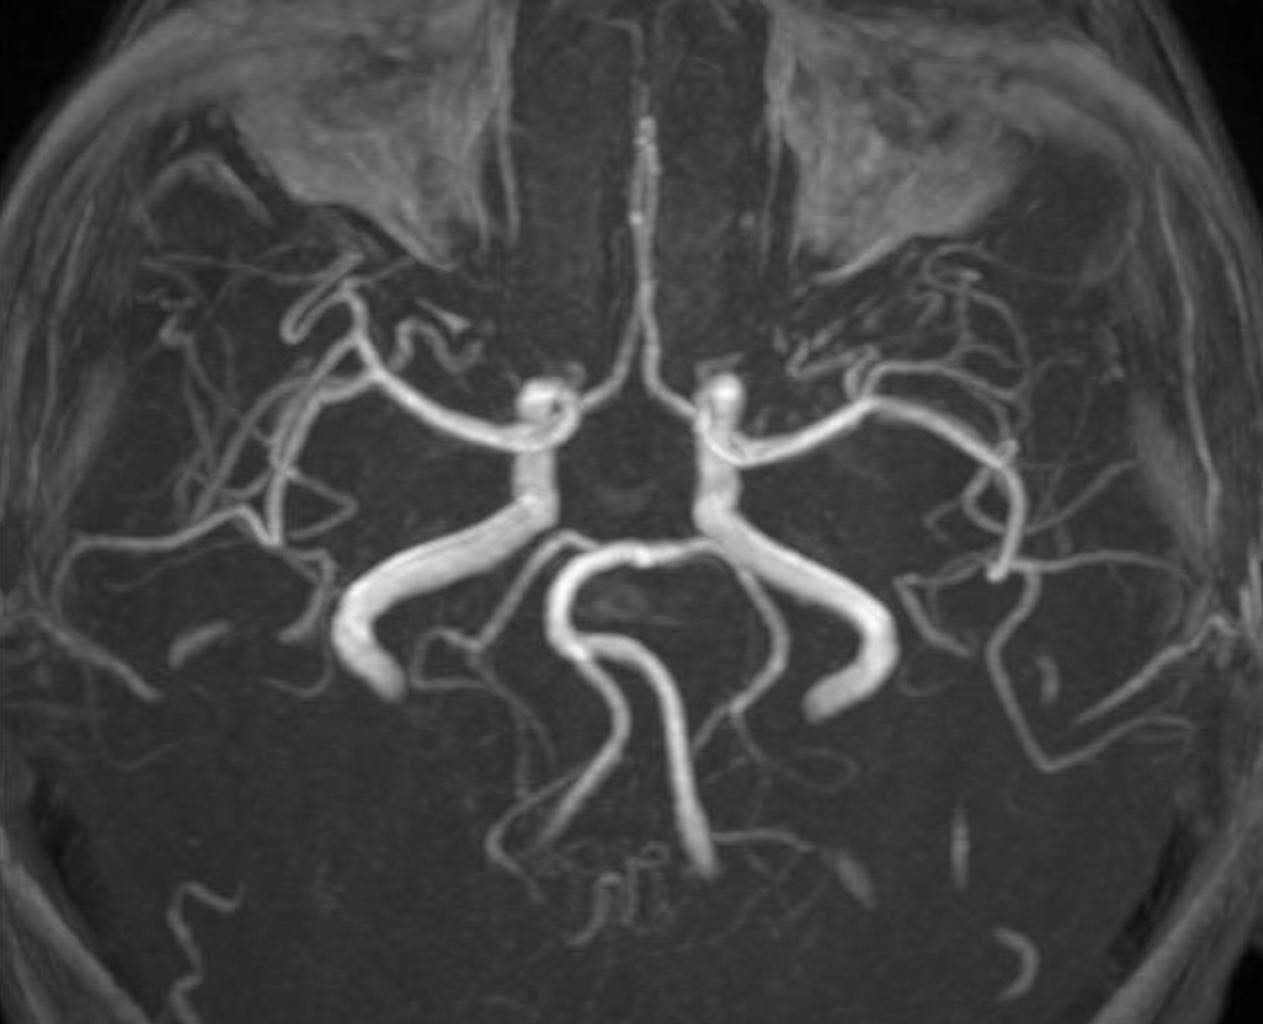

Hình ảnh kiểm tra mạch máu não của người bệnh không ghi nhận tình trạng tắc hoặc hẹp các mạch máu lớn (ảnh: BSCC)

PGS Huy Thắng cho biết, ngay khi nhập viện, người bệnh được chụp MRI não. Hình ảnh cho thấy tổn thương não xảy ra ở hai bên trung tâm bán bầu dục và vùng lồi thể chai. Các thăm dò mạch máu não không ghi nhận tình trạng tắc hay hẹp các động mạch lớn. Dựa trên lâm sàng và hình ảnh học, các bác sĩ chẩn đoán bệnh nhân bị nhồi máu não cấp vùng trung tâm bán bầu dục hai bên và lồi thể chai.